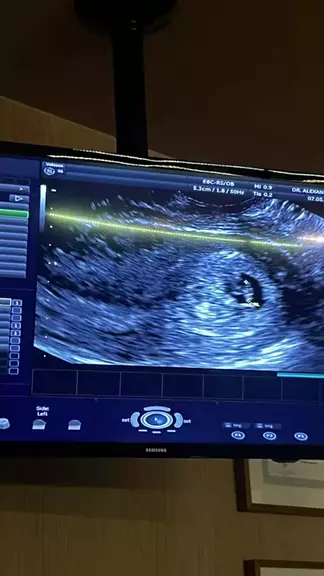

Qual dia da semana você está assistindo esse vídeo?📅 #gravidez #Dramacoreano #diadonordestino #SequênciaFeiticeiraNoKwai